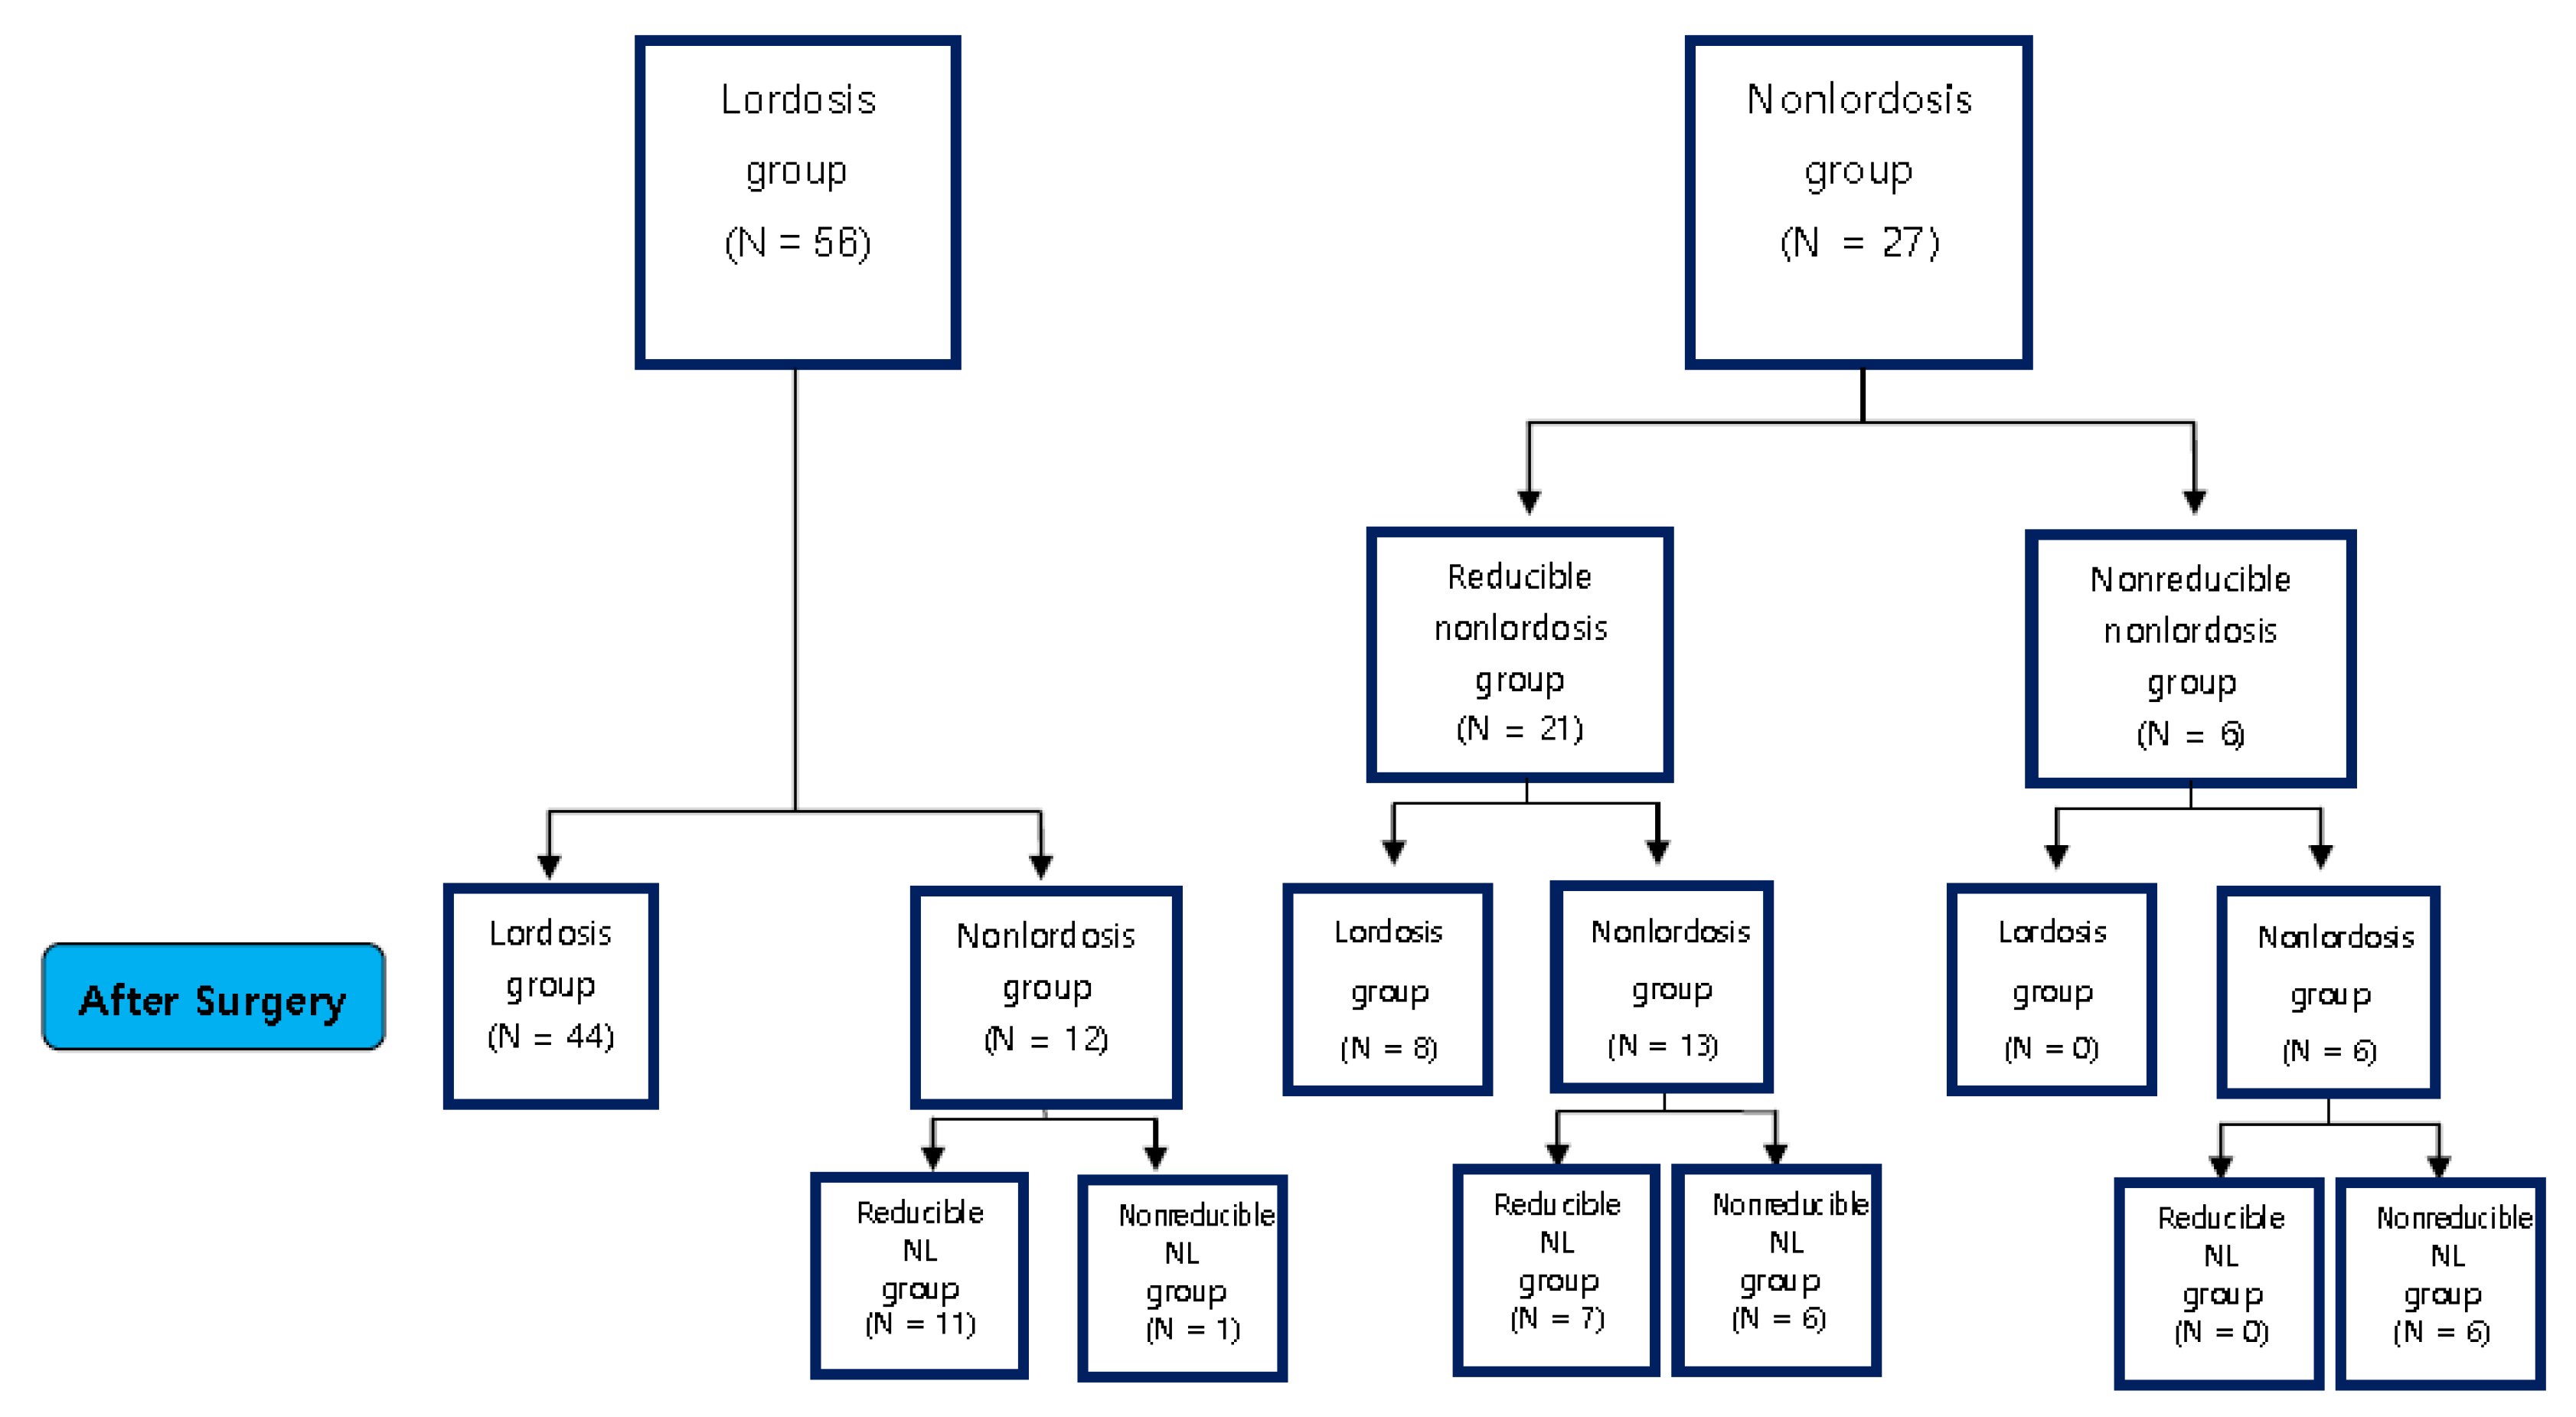

3.1. Post Operative Change of Curvature